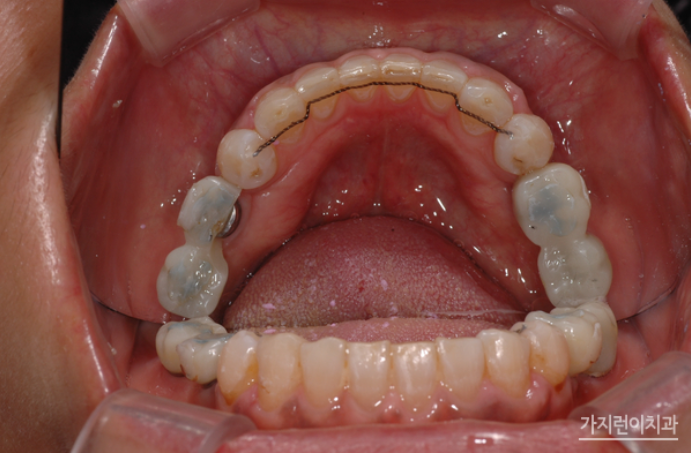

두 개의 와이어를 이용한 탄댐설측교정

특히 본원에서는 안정적인 교정을 위해 상악 설측교정 장치는 두 개의 와이어를 사용하는 탄댐설측교정을 진행했습니다. 교정과 임플란트를 병행 했음에도 결과를 보면 안정적인 구치부 교합을 만들었다는 것을 확인할 수 있었는데요. 임플란트는 고정이 되기 때문에 교정이 아주 약간만 틀어져도 틈이 벌어지는 등의 문제가 생길 수 있습니다. 그래서 계획대로 치아이동이 잘 되어야 했었는데요. 사진을 보면 지정된 위치에 임플란트가 식립되어 조화로운 치열과 교합 상태로 완성된 것을 볼 수 있습니다.

환자 분은 교정이 끝난 후 꾸준히 정기검진을 받아보고 계신데요. 3년이 지난 날에도 교합이 안정적으로 유지된 것을 확인할 수 있었습니다.